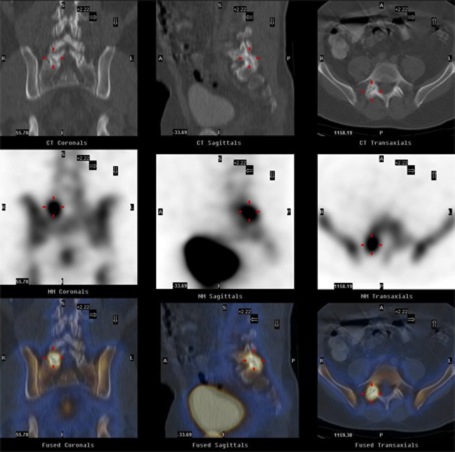

The following picture shows a series of images* taken by WBNM’s Hawkeye:

- The top row of images shows the low-dose CT scans in the coronal, sagittal and transverse planes.

- The middle row shows the corresponding nuclear SPECT images.

- The bottom row shows the fused SPECT/CT display.

The image series clearly demonstrates that the patient's back pain was due to active facet joint arthritis, which WBNM’s Hawkeye accurately localised in the right side of the fifth lumbar vertebra. These precise images enabled WBNM to target specific treatment to the exact site.

* The image quality shown above has been reduced to allow the images to load quicker on the internet. The scans available to WBNM are of considerably higher resolution.